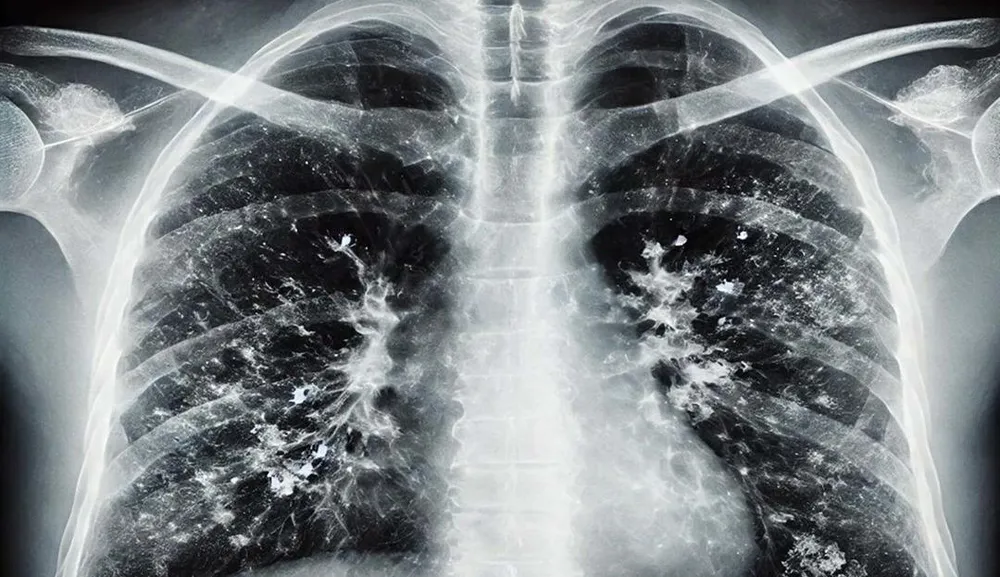

Prof. Dr. Şener, süperenfeksiyonların zatürre, pnömoni ve akciğer iltihabı gibi ciddi durumlara yol açabileceğini belirterek, “Bu tablolar hastaneye yatış, oksijen desteği ve yoğun bakım gerektirebilir. Bu nedenle grip sonrası belirtiler devam ediyorsa mutlaka doktora başvurulmalı” uyarısında bulundu.

Özellikle 65 yaş üstü vatandaşlara yönelik uyarılarda bulunan uzman, RSV enfeksiyonlarının akciğerde yaygın inflamasyon oluşturduğunu ifade etti. “RSV aşısı mevcut. Ücretli olarak yaptırabilirsiniz ve özellikle 75 yaş üstü bireylerin aşılanması hayati önem taşıyor. 65 yaş üstü grupta viral enfeksiyonlar ağır seyrediyor. Ciddi solunum yetmezliği, ateş ve titreme gibi belirtiler acil müdahale gerektirebiliyor” dedi.

Prof. Dr. Şener, hastalığı hafif geçiren kişilerde de risklerin devam ettiğine dikkat çekti. “Hafif geçirilmiş grip sonrası akciğerlerde hasar oluşabilir ve ilerleyen dönemde KOAH veya astım gibi kronik tablolar ortaya çıkabilir. Kalp hastalığı, hipertansiyon ve diyabeti olanlar da ağır klinik seyir gösterebilir. Grip sonrası öksürük ve balgam devam ediyorsa bu süperenfeksiyonun işareti olabilir. Bu durumda antibiyotik tedavisi gerekebilir” diye konuştu.